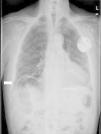

Hepatodiaphragmatic interposition is generally diagnosed by plain X-ray. The typical image shows air below the diaphragm, with visible haustra between the liver and surface of the diaphragm (Fig. 1). In case of diagnostic uncertainty, the location of the air will not change when the patient changes posture.

Differential diagnosis should be made mainly with pneumoperitoneum, typically seen on X-ray as a half-moon shape extending below the diaphragm, with no visible haustra, and which changes with posture.